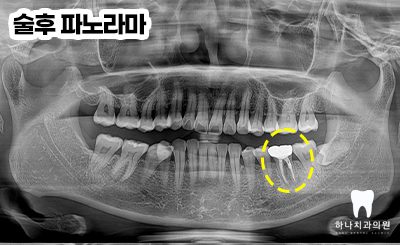

4회에 걸쳐진 치료를 완료하고

근관의 완전한 확보, 세척, 충전을

완료한 뒤 마무리 후 본뜨기 전의 모습입니다.

앞으로 2년 이상의 염증 부분의

잇몸뼈 리모델링 기간을 거쳐야

성공했음을 확신할 수 있다고